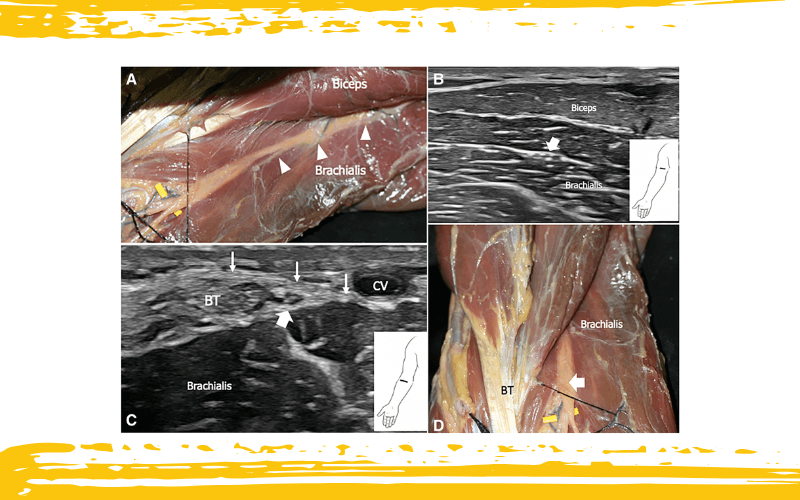

Disección anatómica con correlación ecográfica del nervio cutáneo lateral del antebrazo (LCNF) en el tercio distal del brazo.

La disección anatómica en A muestra el LCNF (cabezas de flecha blancas) entre el braquial y el bíceps (este último desplazado radialmente).

En B, la imagen ecográfica demuestra el LCNF (flecha blanca) en la misma disposición anatómica que en A.

La imagen ecográfica en C se obtiene más distal, donde el LCNF atraviesa la fascia en el lado lateral del tendón del bíceps (BT), medial a la vena cefálica (CV).

En D, se presenta la disección anatómica correspondiente del LCNF, tal como se observa en la imagen ecográfica B.